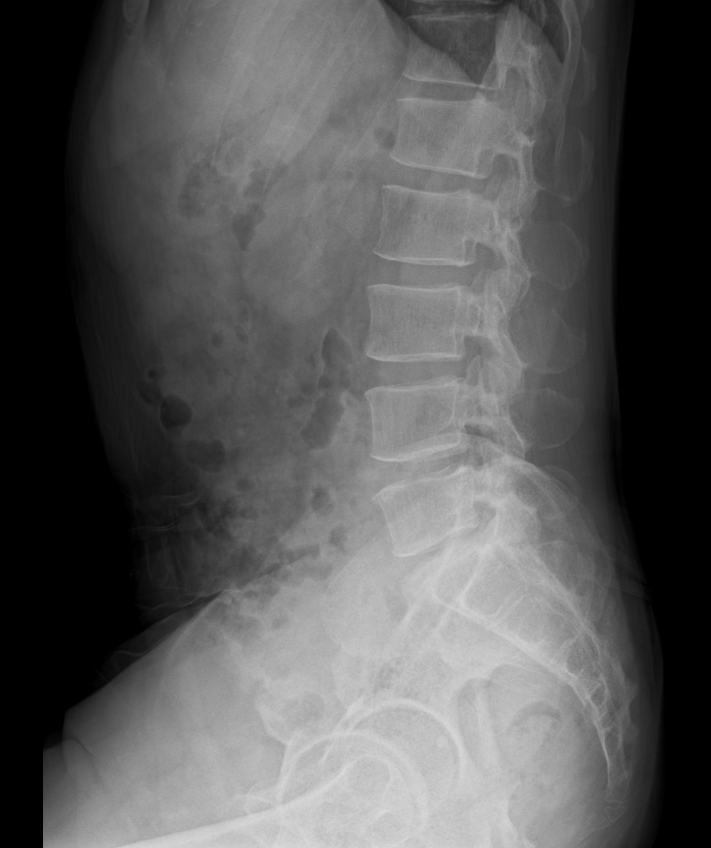

X-ray는 뼈의 형태나 골절을 확인하기 위한 영상 검사입니다.

뼈가 부러졌거나 탈구된 경우에는 분명히 도움이 되지만, 근육·인대·힘줄과 같은 연부조직 손상(즉, ‘삠’이나 근육통)은 X-ray에 전혀 나타나지 않습니다.

목이나 허리의 경우에도 척추가 일시적으로 경직된 모습을 통해 간접적으로 염좌를 추정할 수 있을 뿐, 염좌 그 자체를 확인할 수는 없습니다.

따라서 골절이 의심되지 않는 상황에서 X-ray로 얻을 수 있는 정보는 거의 없다고 할 수 있습니다.